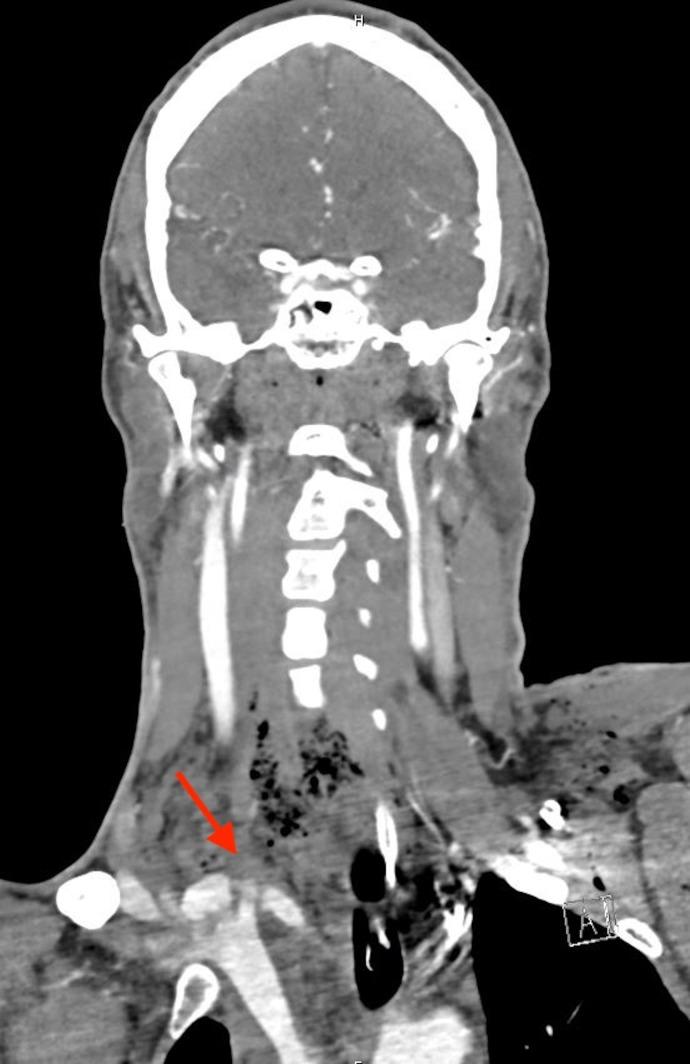

Traumatic subclavian artery injury with a pulmonary artery bullet embolism.

https://cdn.ncbi.nlm.nih.gov/pmc/blobs/dd41/10900316/571dcb0d49b6/tsaco-2024-001368f01.jpg